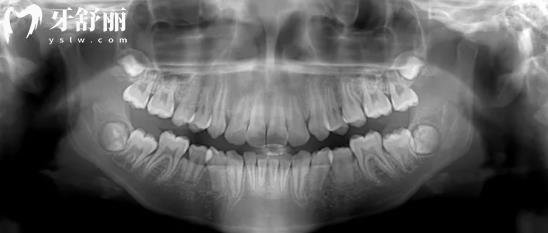

根据全景片如何判断有没有蛀牙?

有的牙齿在表面上是小黑点其实内部已经龋坏不少了,但是光靠肉眼是看不出来的,所以需要经过x光照射成像判断牙齿内部的龋坏情况。

一般的牙齿是灰色的,下部中间有条黑线那是牙髓腔,如果是牙冠的位置有黑色阴影而且较为明显的话那就是龋齿的范围了。如果是已经修补过的牙齿能在全景片中清晰看出修补材料的痕迹。

全景片还可以观察牙周情况,比如牙齿之间的缝隙大而且是黑色的,牙体看起来长一般的情况下可能患有牙周病,因为牙龈已经开始萎缩,牙槽骨被吸收所以牙齿慢慢开始裸露。因此可以看整体的口腔条件是否适合做种植牙手术,